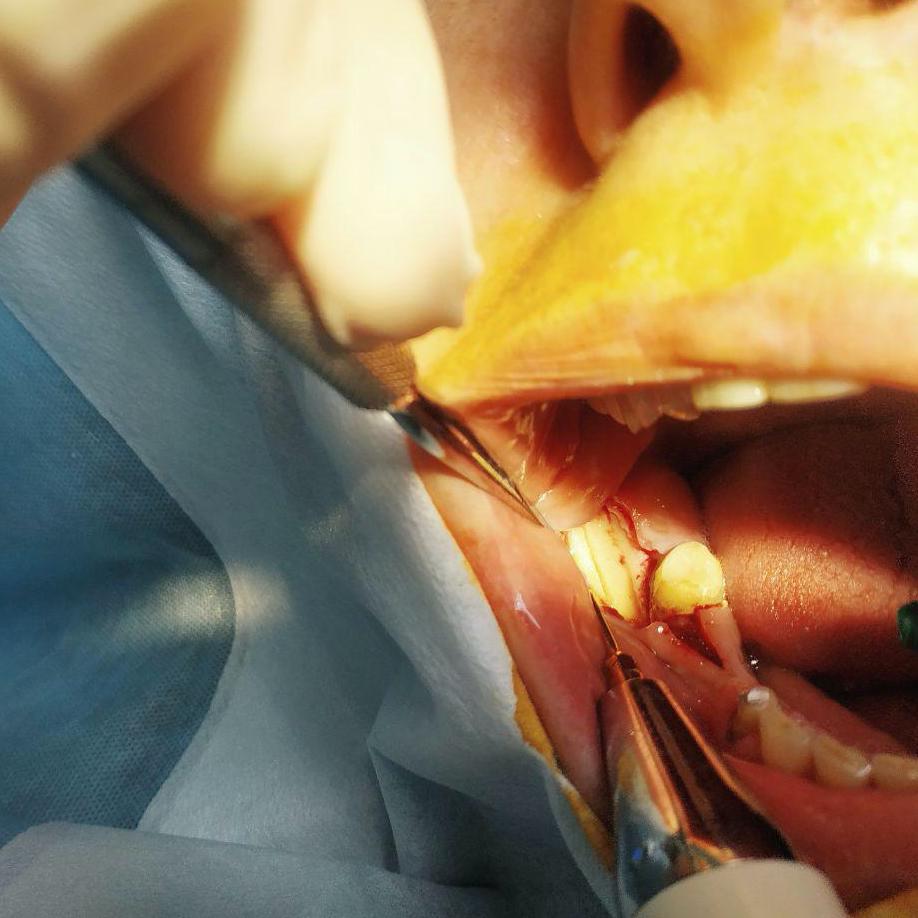

Лечение: Принято решение о пересадки ее собственной кости из угла челюсти. Отслоение слизисто-надкостничного лоскута. Забор блока кости в области угла челюсти. Остеопластика блоками + ксенографт. Установка двух имплантов. Наложение швов.